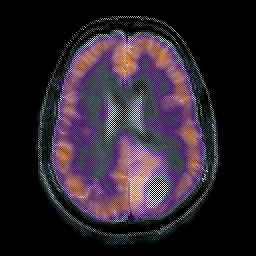

Glioma overlay -- Slice #18

[Home][Help][Clinical] Slice 18